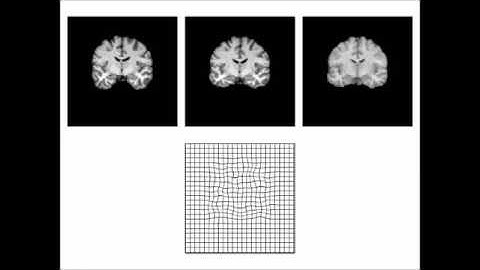

3D non-linear image registration using Ezys